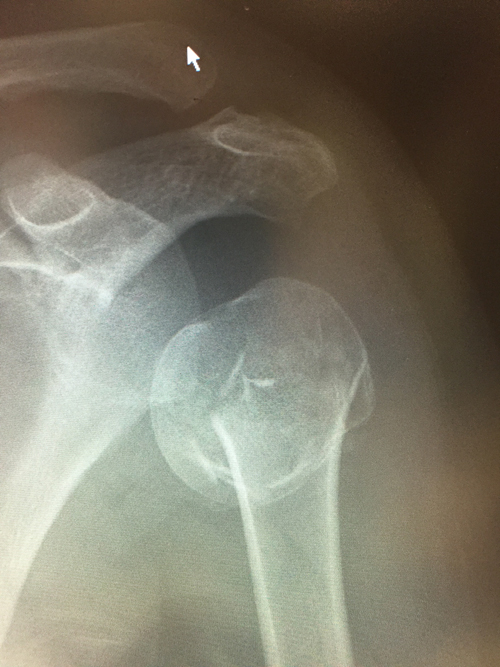

Proximal Humeral Fracture

They may occur following a simple fall in patients with osteoporosis or at the other extreme happen at a high velocity as in a motorcycle accident in a young patient with normal bone density.

The majority of these fractures are diagnosed with appropriate x-rays. If there is any doubt as to the fractures complexity as in when surgery is being contemplated a CT scan may be of help. MRI is only helpful in diagnosis if no fracture is seen on x-ray as it may detect undisplaced fractures or rotator cuff damage.

The majority of proximal humeral fractures are treated conservatively. Surgery is indicated for very displaced fractures or those associated with a dislocation. Conservative treatment is by using a sling to support the shoulder for the initial 6 weeks. This sling can be removed in a safe environment to allow the arm to rest straight by the side allowing showering. Active movement is avoided for the 6 weeks.